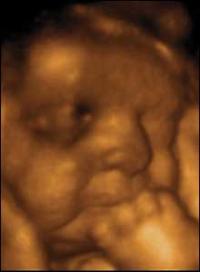

Вот на этом снимке видимо трехмерное УЗИ: